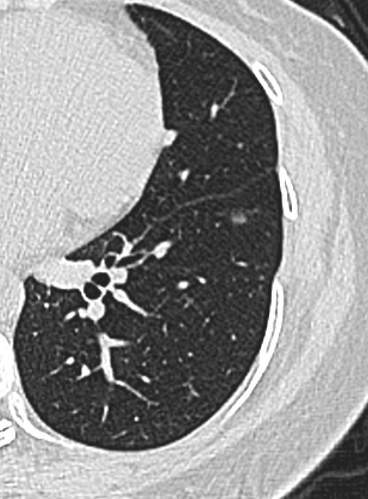

中年女性,既往体健。

21年底左下肺,直径5.2mm: